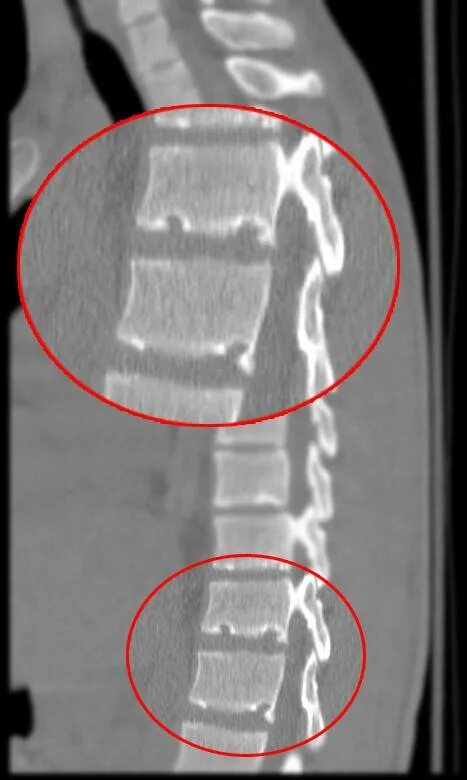

Что значит грыжа шморля